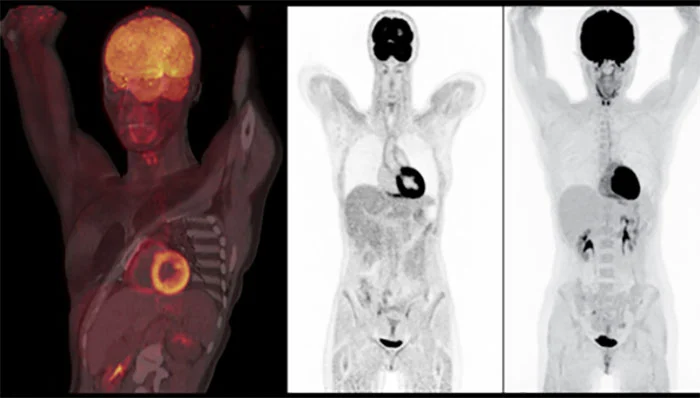

El estudio PET-CT es una técnica diagnóstica que ofrece una combinación de una imagen de tomografía por emisión de positrones (PET) con una imagen de tomografía computarizada por rayos X (CT). Las dos técnicas aportan distinta información sobre el cuerpo humano. el PET es una prueba que permite obtener imágenes de la función celular para evidenciar las diferencias entre el tejido sano y el enfermo, mientras que la CT aporta imágenes, que permiten la localización anatómica precisa de las anomalías observadas en el PET.  Estos sistemas permiten corregir la atenuación mediante la obtención de imágenes de rayos X, asi com también fusionar ambas modalidades  para dar información duncional y anatómica,  para la obtención de las imágenes no solamente es necesario contar con el  equipo PET-CT    pues no funciona por sí mismo para obtener imágenes sin que al paciente se la haya sumistrado via endovena el radiofármaco.

En determinadas áreas corporales como el cerebro, miocardio o hígado, se observa un acumulo fisiológico de 18F-FDG, mayor que en otros órganos, pero es en los tejidos tumorales, donde se detecta la mayor retención de 18F-FDG debido al incremento del metabolismo glucídico en las células malignas. Para la medición de la captación del radiofármaco y con ello de la actividad metabólica tumoral se utiliza el valor de captación estándar (SUV o Standardized Uptake Value), que se define como el cociente entre la captación de FDG en la lesión y la captación media en el resto del organismo. El equipo PET funciona en base a la detección de los rayos gamma de 511 keV.